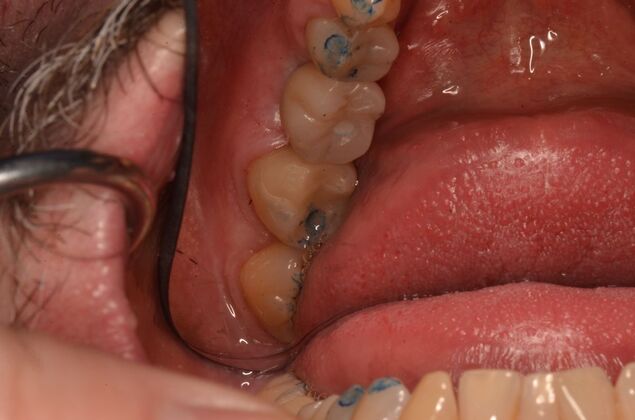

Patient lost lower first molars and required two lower implants with two lower screw retained crowns